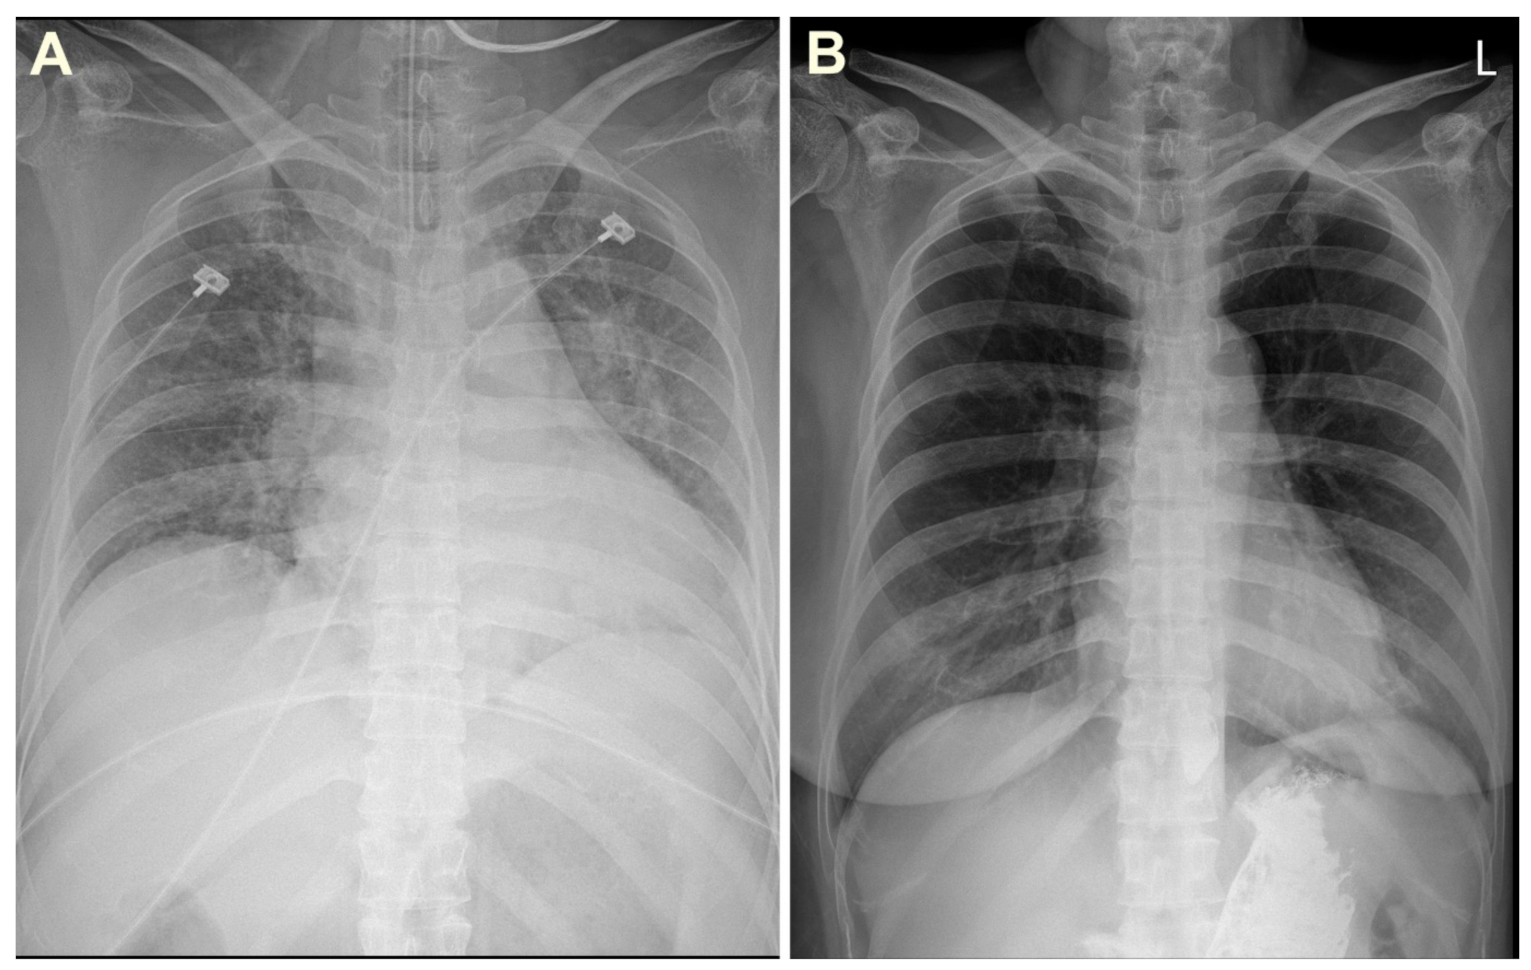

In the emergency department, her initial blood pressure was 112/79 mmHg; pulse rate, 107 beats/min; respiratory rate, 20 breaths/min; axillary temperature, 36.0 °C; and peripheral oxygen saturation, 50% measured by a pulse oximeter. Chest auscultation revealed crackles in both lungs. The initial white blood cell count was 11.17 × 103/μL with 58.1% neutrophils and 0.5% eosinophils. The results of arterial blood gas analysis were: pH, 7.010; PaCO2, 84.8 mmHg; PaO2, 61.4 mmHg; and HCO3̄, 15.4 mmol/L. The serum glucose concentration was within normal range (130 mg/dL); the sodium level was normal (138 mmol/L); the potassium level was elevated (5.6 mmol/L); the calcium level was normal (8.9 mg/dL); the aspartate transaminase and alanine transaminase levels were normal (32 U/L and 17 U/L); the ammonia level was normal (32 μmol/L); and the lactic acid level was normal (1.5 mmol/L). The patient did not have acute inflammatory signs such as being febrile or chilly, and the high-sensitivity C-reactive protein level was also within normal range (0.24 mg/dL). No evidence of peritonitis was observed in the peritoneal fluid analysis. The initial chest radiograph showed diffuse severe pulmonary edema with peribronchial infiltration and subsegmental atelectasis (Figure 2A).

Figure 2.

Chest radiographs on admission (A) and discharge (B).

Upon emergency department arrival, her mental status was drowsy and she was in a state of respiratory failure; therefore, intubation and invasive mechanical ventilation were immediately performed. The patient’s vital signs fluctuated; thus, PD was discontinued, and CRRT was initiated (target clearance dose: 35 mL/kg/h) in the intensive care unit to remove blood tetramine and control volume status (Figure 3). Her symptoms gradually improved, and mechanical ventilation weaning succeeded on the 5th day of admission. CRRT was switched back to PD on the 10th day of admission. She fully recovered without pulmonary edema (Figure 2B) and was discharged on the 15th day after admission.